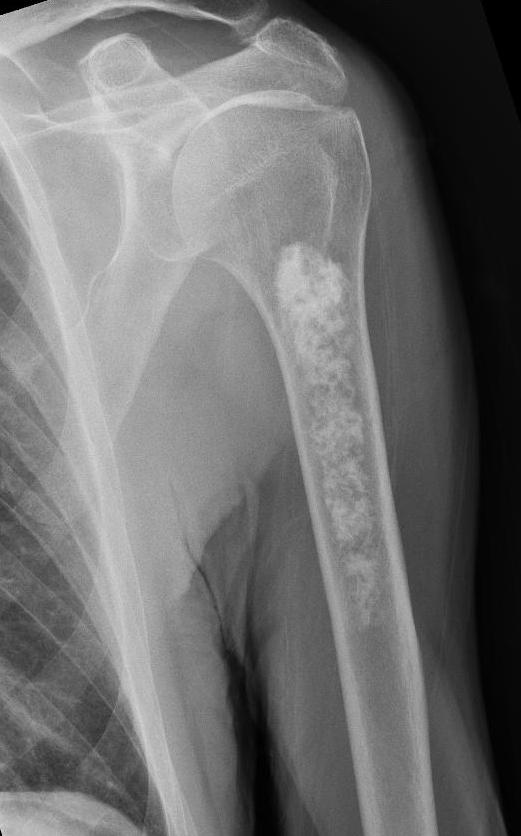

röntgenfoto van de arm

Een 82-jarige man werd verwezen naar het ziekenhuis vanwege valneiging. Uit de anamnese en het lichamelijk onderzoek kwamen geen relevante bijzonderheden naar voren. Bij de analyse van de valneiging werd routinematig een röntgenfoto van de thorax gemaakt. Hierop werd bij toeval een afwijking in linker humerus gezien.